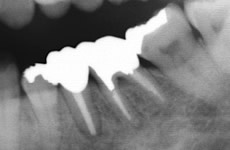

根の先の病気

主に虫歯が原因で、細菌が歯の中に通っている神経の管を通って神経自体に炎症を起こしたり、根の先に膿を作ることがあります。感染してしまった部分をきれいにとり、清掃をして、きれいになったところで細菌が増えないように薬をつめます。

当院では ラバーダム防湿法 を用い、マイクロスコープ下にて治療を行っております。